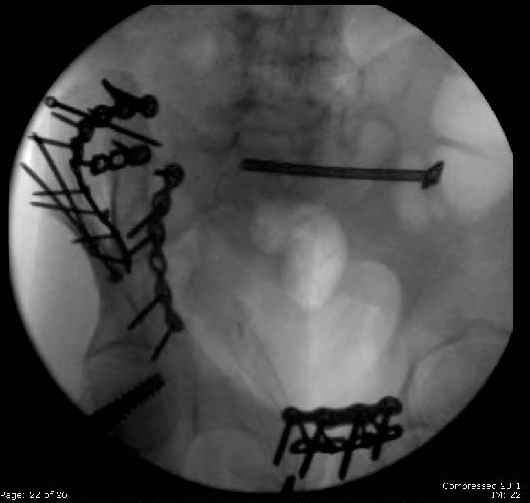

Here are the postop fluoros.

Symphysis then 'fine-tuned' & reduced as close as possible to anatomic (but, still with forward rotation of R hemipelvis - or, is it extension?) Accepted that amount of deformity and plated symph

with 4-hole symphyseal plate.

Fluoroed L SI joint and it seemed stable, but wide. So, applied c-clamp to try to squeeze down L SI joint (and note, on the last slide attached, that it's still wide), and got it closer. Single perc Iliosacral screw 40mm thread.

Applied second plate anteriorly on symphysis as I wasn't confident L SI was as stable as it could be and wanted to protect it better.

Finally, the L SI joint seemed wide, even after closing it with c-clamp and iliosacral screw, so I added the extra 4 hole symphyseal plate anteriorly (even though to my knowledge unproven). That was the thinking and sequence of events that lead to the 2 symph plates shown. Note that the 4 hole recon is a locking plate (non-locked in medial 2 holes before locked screws in holes 1 & 4) -- fertile ground for debate on that I'm sure!